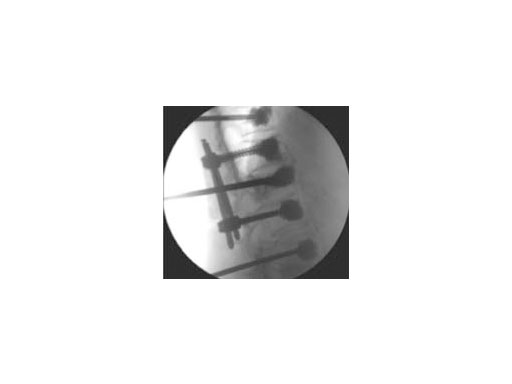

Both guide wire and trocar can be inserted through either a transpedicular (Fig 2a) or extrapedicular (Fig 2b) approach. The trocar allows access in a single step while the wire guide is first used to create a path for the access instruments.

The controlled inflation of the balloons allows you to reduce the fracture and create a cavity in the cancellous bone. This containment can subsequently be filled using a legally-marketed bone filler adequately indicated for kyphoplasty and/or vertebroplasty procedures, to stabilize fractures in the vertebral body, prevent further collapse of the vertebra, and to reduce pain (Fig 6). The direction of the bone filler flow can be changed by orienteering the handle of the injection needle with the side opening.